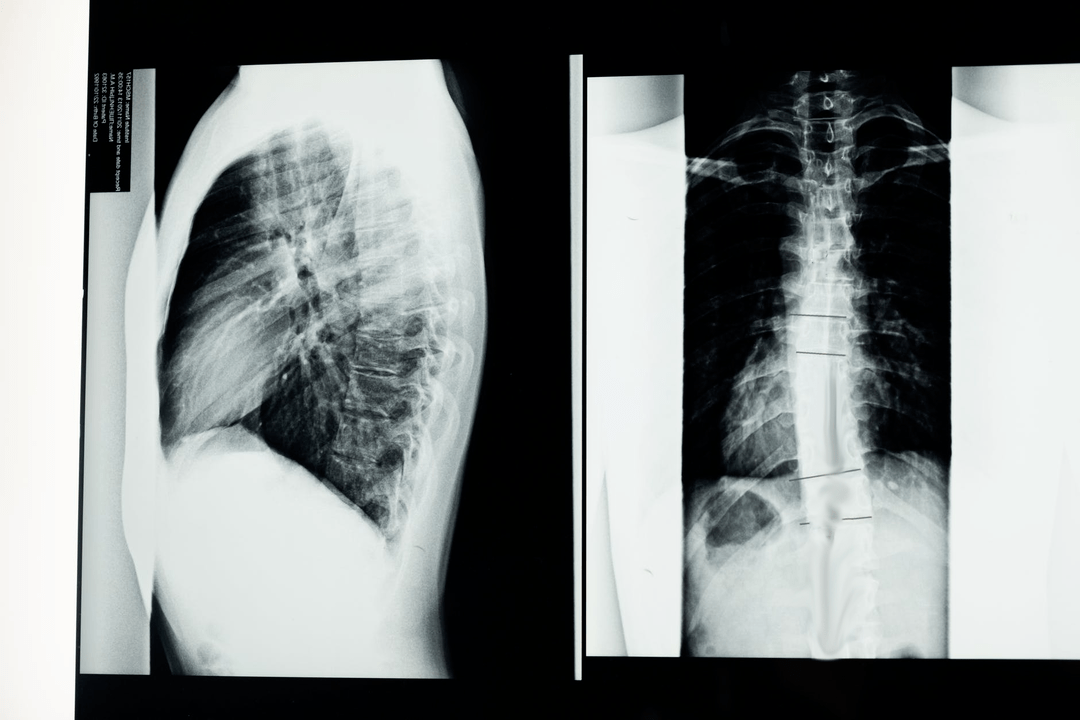

Antes de comezar os estudos diagnósticos, o neurólogo recolle o historial médico do paciente e estuda coidadosamente as súas queixas. A osteocondrose ten síntomas comúns con algunhas outras enfermidades, polo que é importante poder diferenciar patoloxías. Os estudos de raios X axudarán a confirmar o diagnóstico de osteocondrose: radiografía, mielografía e tomografía computarizada.

Unha radiografía de enquisa permítelle obter unha imaxe de raios X da columna vertebral ou unha sección dela. Deste xeito, o médico pode determinar a localización afectada pola enfermidade. Para máis claridade, explicaremos como se pode determinar a osteocondrose mediante raios X: a imaxe mostrará un estreitamento do disco intervertebral, a presenza de crecementos óseos (osteofitos) ou un cambio na forma do segmento espinal.